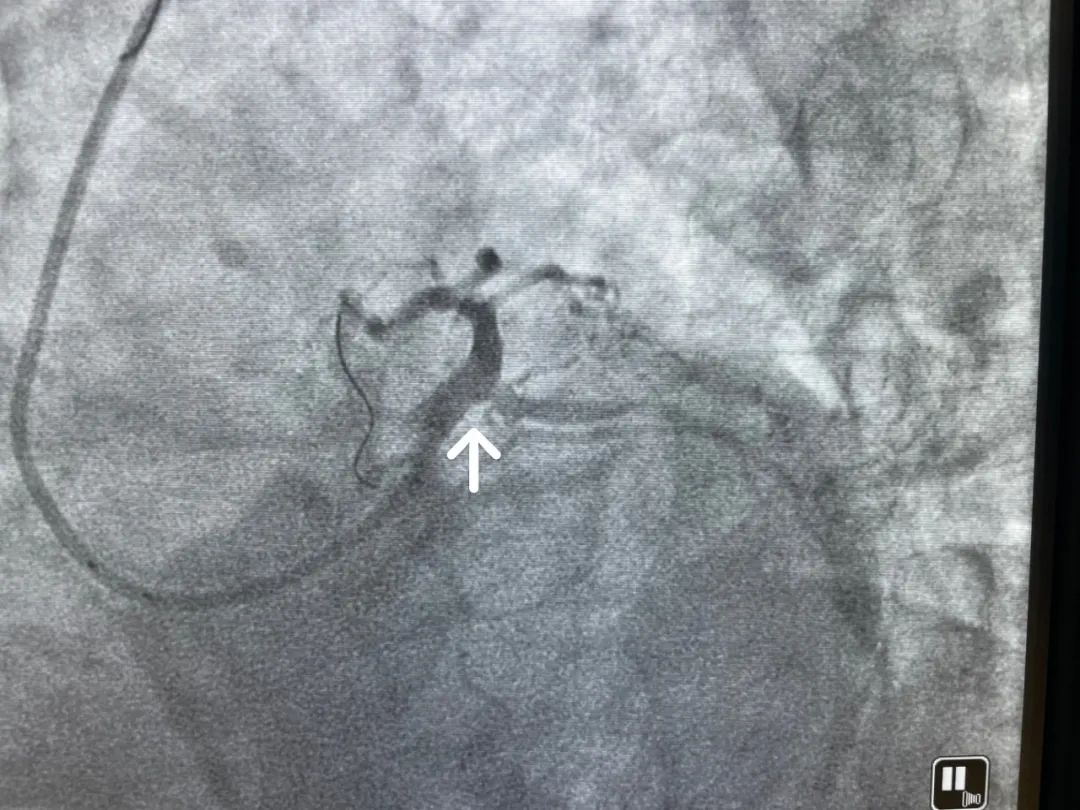

▲左主干重度狹窄部位

經(jīng)詳細(xì)檢查后發(fā)現(xiàn),H大爺心臟處左主干病變,提示左主干遠(yuǎn)段重度狹窄,情況十分兇險(xiǎn),如不盡快治療,隨時(shí)都有心臟驟停、心源性猝死的巨大風(fēng)險(xiǎn)。性命攸關(guān),心血管內(nèi)科團(tuán)隊(duì)立即為患者制定詳細(xì)手術(shù)方案,準(zhǔn)備對大爺開展左主干支架植入術(shù)。

在心血管內(nèi)科桑學(xué)東主任的指導(dǎo)下,很快手術(shù)便開始了,在冠脈造影下明確可見左主干遠(yuǎn)段基本堵塞,心血管內(nèi)科團(tuán)隊(duì)通過運(yùn)用細(xì)如發(fā)絲的導(dǎo)管導(dǎo)絲深入血管,精準(zhǔn)找到堵塞部位,進(jìn)球囊、釋放支架等,通過精湛的技術(shù)多次操作為患者打通堵塞的血管,讓閉塞的血管即刻恢復(fù)3級血流。當(dāng)屏幕上的冠脈造影顯示血液流通的影像,手術(shù)順利結(jié)束。